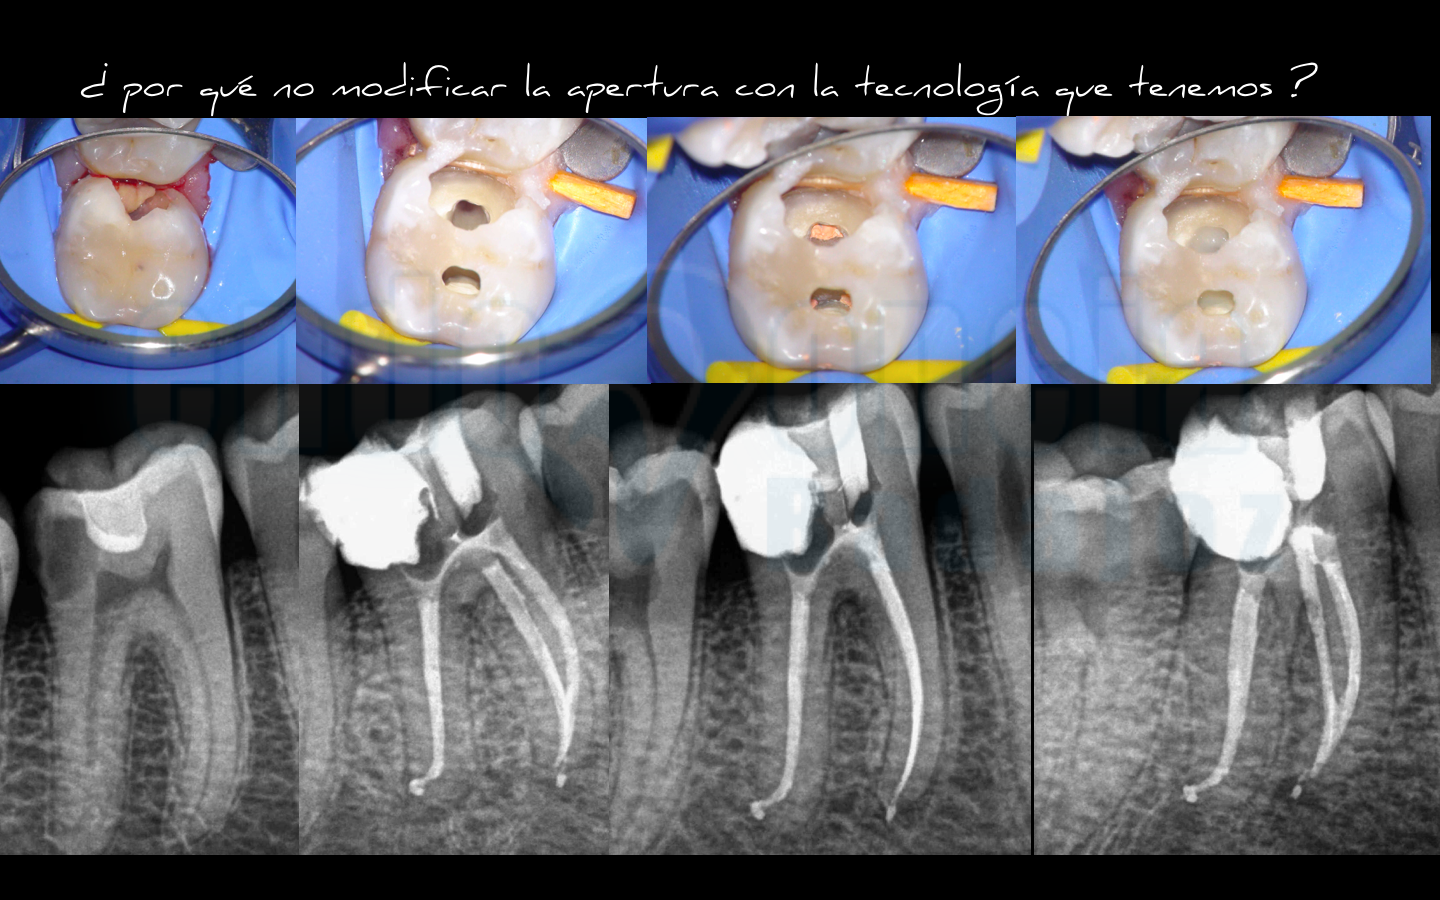

El caso que muestro hoy, es un familiar ( aunque trate a todos los pacientes por igual ) quiero demostrar que esta práctica la realizo con todos los que creo que está indicado o puede estarlo.

Lo que intentamos es estudiar el caso, como cualquier otra especialidad odontológica, para ver de que manera es la más beneficiosa para el paciente, sabiendo que debemos realizar un tratamiento endodóntico correcto y eficaz, pero que por desgracia depende en gran medida de la estructura remanente dentinaria , por lo que también debemos pensar en ello.

Así que , teniendo presente la complejidad anatomica de estas piezas, por lo que no en todas las piezas lo podemos hacer ( de ahí, que debamos estudiar el caso), decidimos intentar ser lo más conservador posible intentando conseguir  un equilibrio entre en un buen tratamiento de conductos y mantener la mayor cantidad de tejido dentinario.

Captura de pantalla 2016-06-21 a las 20.18.09